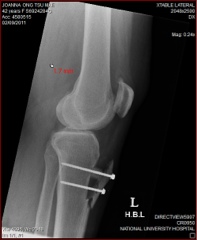

A long and painful journey to recovery

"Tibial Tuberosity Elevation", my orthopedic surgeon Assoc Prof SN chimed almost melodiously when I asked what he was planning to do with my wonky knee. To which I replied quizzically, " Table Testicular what?".

That was about 6 months ago just after I was diagnosed with a severe patella tilt - or for the uninitiated - a shifted kneecap. Years of callousness as a contact rugby player, and even more years of gungho 10km races thereafter were to blame. Compounded with months of stubbornness by skipping physiotherapy sessions after the surgery and pushing myself at the gym in spite of Prof's advice to stop doing weight training, my knee is going through "menopause". Sometimes it plays up with alot of pain, and sometimes it's ok. I think it's still a long journey to recovery. Prof promised that I will be pretty much recovered after a year. However, much as I would like to compete again in the Women's 10km run in a few months time, I might have to sit out this one.

Next week, I will be traveling to Siem Reap for a week long vacation. It would be an interesting test of my patience at the airport security gantry if the metal detectors are set off by my knee implants. Note to self: Bring that medical card that can possibly help explain to these over-zealous airport security chaps that I am not carrying a gun. I will always remember what Prof said to me 2 weeks after my surgery, and when he found out that I went grocery-shopping with my crutches just 3 days after my surgery, " Joanna, the metal implants in your knee weren't placed in there to make you bionic."